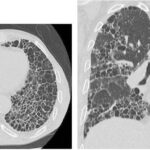

この抗ビンキュリン抗体が小腸を攻撃するため、小腸の蠕動運動が悪くなり、大腸の細菌が流入してSIBOとなり、その結果としてガスや下痢などを発症するIBSとなります。

腸神経の損傷とカハール介在細胞(ICC)および遊走運動複合体(MMC)が適切に機能しない場合、腸内細菌叢が破壊されます。大腸の腸内細菌叢は、腸内の何十億ものバクテリアで構成されており、バランスが取れていると、腸を健康に保ちます。